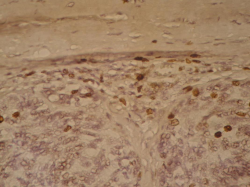

Стадии меланомы показывают, насколько образование проросло в кожу, и распространяется ли оно. Врачи используют 2 шкалы, чтобы определить глубину меланомы. Это шкала Кларка и шкала Бреслоу. По шкале Кларка, выделяют 5 стадий прорастания. Степень поражения показывает, в какие слои кожи проникло образование. Чем выше цифра, тем глубже прорастание.

| I | Клетки меланомы локализуются в эпителии | 100% |

| II | Образование разрушает базальную мембрану и проникает к сосочковому слою | 72% |

| III | Меланомой заполнен сосочковый слой | 45% |

| IV | Образование проникает в ретикулярный слой, приближается к подкожным тканям | 31% |

| V | Распространение в клетчатку под кожей | 12% |